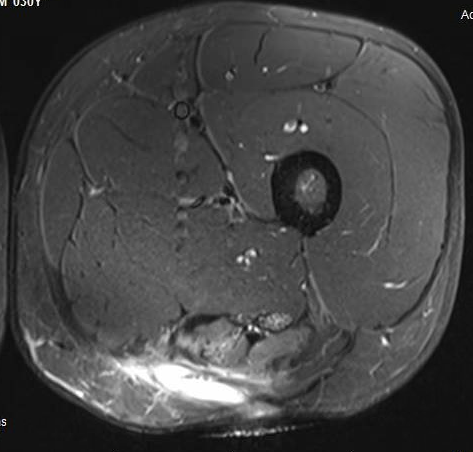

Proximal hamstring avulsion, with tendon floating in hematoma / seroma

Incomplete tears

High grade partial tear proximal hamstring